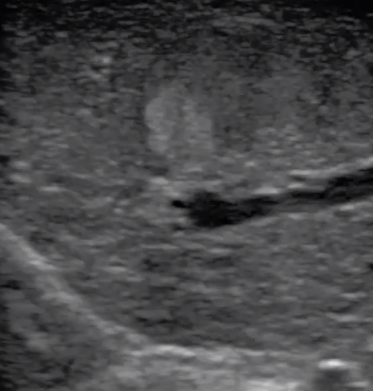

多數(shù)的生殖科醫(yī)生對于受精卵的植入采用憑經(jīng)驗操作或是使用傳統(tǒng)腔內(nèi)探頭引導(dǎo),同樣存在手術(shù)空間小、受精卵放置位置不確定等風(fēng)險。專業(yè)的宮腔專用探頭,配合專用的窺器使用,為醫(yī)生提供最大的手術(shù)視野。

胎移植臨床圖